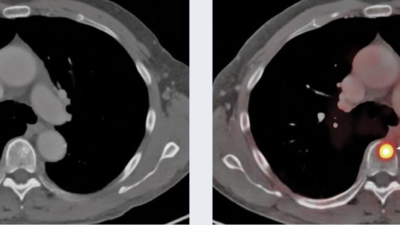

medical imaging